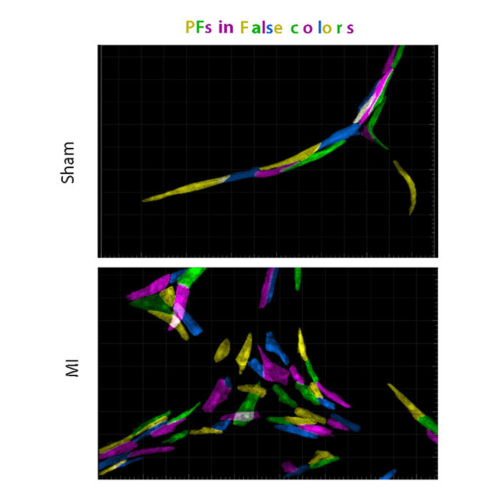

Cardiac defects in a mouse model of Duchenne dystrophy (Mdx)

New study challenges the link between Purkinje fibers and heart arrhythmias in Duchenne muscular dystrophy.

Cardiac regeneration is not as perfect as it has been claimed

Cardiac regeneration leads to hyperplastic Purkinje fiber network in association with ventricular conduction disorders.